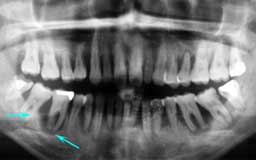

Hさん 初診時 53歳 男性

50歳頃まではもう少し歯があったそうですが、歯科医院に行くたびに「歯槽膿漏です」といわ れて抜歯。60歳まで何とか総入れ歯にしたくないという

Hさん 19年後 72歳

上顎の補綴処置と左下の親知らずを抜歯。歯槽膿漏の手術を行うことなく月に1度の歯石除去 を継続して行った結果、初診時から大きく変化することなく19年を経過しました